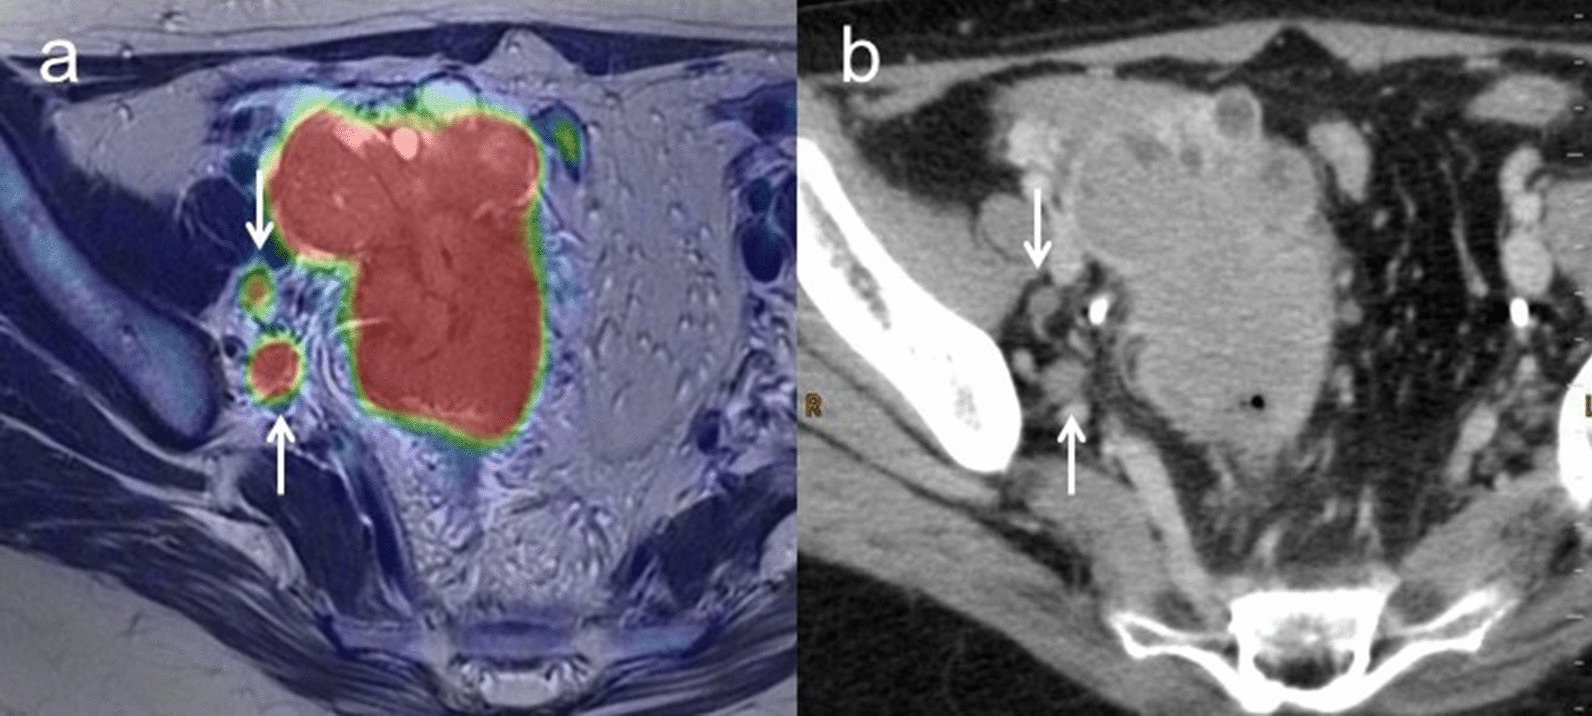

Overall accuracies of T staging for [18F]FDG PET/MRI and ceMRI/ceCT were 96.4% (95% CI 0.96–0.96) (54/56) and 92.9% (95% CI 0.93–0.93) (52/56), respectively (p = 0.48).[18F]FDG PET/MRI understaged the actual T stage in two patients (3.6%), whereas ceMRI/ceCT resulted in understaging in four patients (7.1%).[18F]FDG PET/MRI incorrectly classified one T2b and one T3b tumors as T1, whereas ceMRI/ceCT incorrectly classified one T2a, one T2b and two T3b tumors as T1. Sensitivity, specificity and accuracy for detecting growth into the uterus, fallopian tubes or ovaries were 100% (95% CI 0.43–1.00), 100% (95% CI 0.96–1.00) and 100% (95% CI 0.93–1.00) for [18F]FDG PET/MRI, and 50% (95% CI 0.11–0.50), 100% (95% CI 0.97–1.00) and 96.9% (95% CI 0.92–0.97) for ceMRI, respectively (p = 1.00). Sensitivity, specificity and accuracy for growth into other nearby pelvic organs such as the bladder, sigmoid colon, or rectum were 0% (95% CI 0.00–0.00), 100% (95% CI 1.00–1.00) and 96.9% (95% CI 0.97–0.97) for [18F]FDG PET/MRI and 0% (95% CI 0.00–0.00), 100% (95% CI 1.00–1.00) and 96.9% (95% CI 0.97–0.97) for ceMRI, respectively (p = 1.00). Sensitivity, specificity and accuracy for growth into organs outside the pelvis and no bigger than 2 cm in extent were 95.5% (95% CI 0.86–0.96), 100% (95% CI 0.94–1.00) and 98.2% (95% CI 0.91–0.98) for [18F]FDG PET/MRI and 90.9% (95% CI 0.81–0.91), 100% (95% CI 0.93–1.00) and 96.4% (95% CI 0.88–0.96) for ceCT, respectively (p = 1.00). Sensitivity, specificity and accuracy for growth into organs outside the pelvis and larger than 2 cm in extent were 100% (95% CI 0.92–1.00), 100% (95% CI 0.95–1.00) and 100% (95% CI 0.94–1.00) for [18F]FDG PET/MRI and 100% (95% CI 0.92–1.00), 100% (95% CI 0.95–1.00) and 100% (95% CI 0.94–1.00) for ceCT, respectively (p = 0.00) (Table 5). Figure 2 shows representative images for T2 and T3 staging.

Fig. 2.

a A 67-year-old woman with right ovarian tumor. Axial T2-weighted PET/MR image shows a papillary solid part with FDG uptake invading the posterior uterine myometrium (arrow) in a polycystic right ovarian tumor. b Axial T1-weighted contrast-enhanced MR image shows the papillary solid part with good enhancement (arrow) and unclear findings of growth into the uterus. Histopathologic examination confirmed carcinosarcoma with growth into the posterior uterine myometrium (T2a). c A 62-year-old woman with suspected ovarian cancer. Axial T2-weighted PET/MR image shows the omental cake with FDG uptake (arrow). d Contrast-enhanced CT shows thickening of the omentum with good enhancement (arrow). These findings strongly suggest potential malignancy with carcinomatous peritonitis and histopathologic examination confirmed high-grade serous carcinoma with carcinomatous peritonitis (T3c)

Fig. 3.

a A 50-year-old woman with pathologically confirmed ovarian cancer. Axial T2-weighted PET/MR image shows right pelvic lymph nodes with FDG uptake (arrow). b Contrast-enhanced CT shows right pelvic lymph nodes less than 1 cm in short-axis diameter without enhancement (arrow). After NAC, these lymph nodes are decreased in size and SUV, suggesting these nodes as a sign of malignancy (N1)

M staging

Sensitivity, specificity and accuracy for M staging were 100% (95% CI 0.94–1.00), 100% (95% CI 0.25–1.00) and 100% (95% CI 0.88–1.00) for [18F]FDG PET/MRI, and 25.0% (95% CI 0.19–0.25), 100% (95% CI 0.22–1.00) and 30.8% (95% CI 0.19–0.31) for ceCT, respectively (p < 0.01). ceCT incorrectly classified nine M1 tumors as M0 (Table 5). Figure 4 shows representative images for M staging.

Fig. 4.

a A 66-year-old woman with pathologically confirmed ovarian cancer. Axial T2-weighted PET/MR image shows a right parasternal lymph node with FDG uptake (arrow). b Contrast-enhanced CT shows a right parasternal lymph node less than 1 cm in short-axis diameter with slightly enhancement (arrow). After NAC, this lymph node decreased in size and SUV, suggesting that this node as a sign of malignancy (M1)